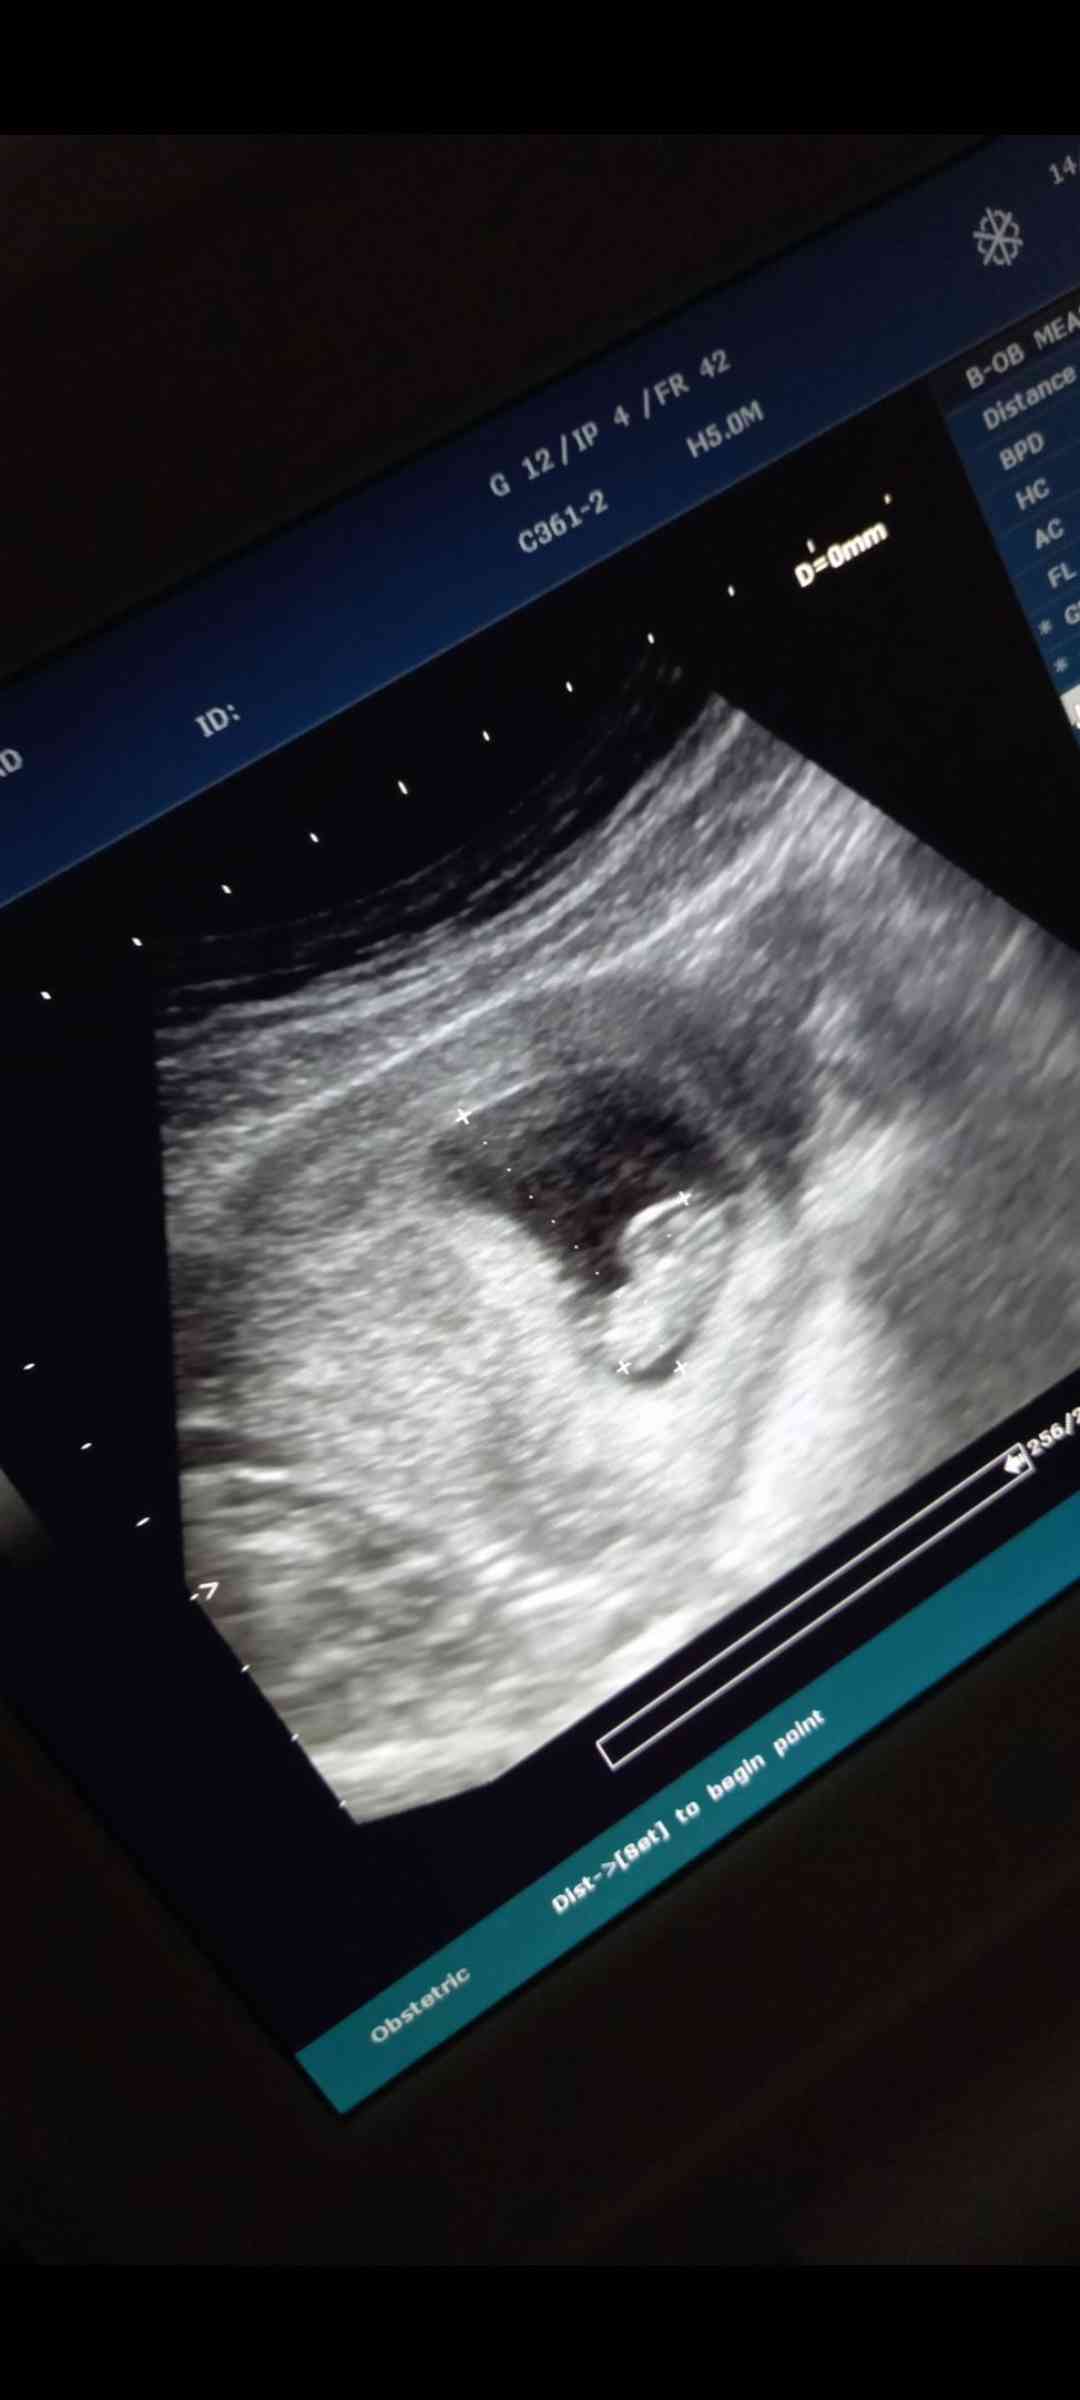

حامل ب الاسبوع ٩ ممكن اعرف شو الجنس